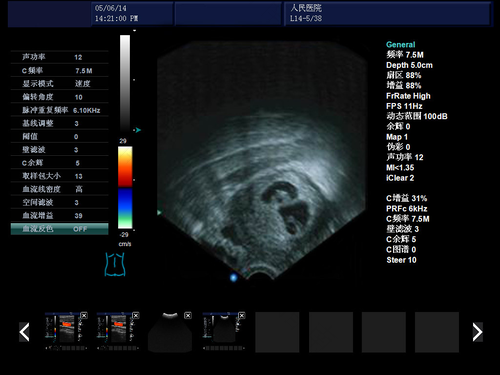

可视人流就是将一根可视的引管插入到女性的体内,将胎儿吸出来,过程很简单,可以将胎儿全部吸出,不容易出现残留的情况。虽然可视人流的安全性比较高,但是女性在做完人流手术一个月之后还是需要到医院重新检查子宫的情况。